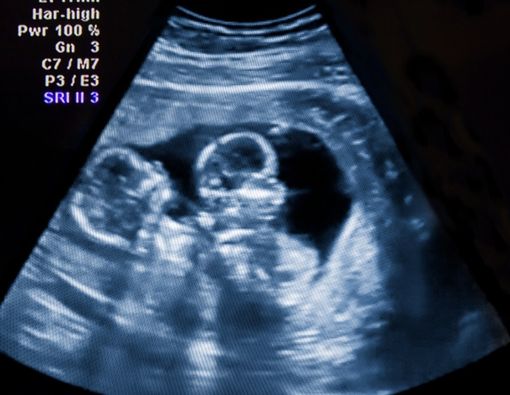

:format(webp)/article/kgFZ-IBkva5c8DYcMx-kC/original/065558700_1606212135-Tanda-tanda-Kehamilan-Kembar-yang-Perlu-Ibu-Tahu-shutterstock_551771494.jpg?w=256&q=100)

Menilik penjelasan di atas, Anda dan pasangan tidak punya gen kembar dalam keluarga tetap punya peluang melahirkan kembar. Pasangan tanpa faktor genetik hanya dapat mengalami kehamilan kembar identik. Sebab, dalam kasus kehamilan kembar fraternal ada faktor genetik yang yang ikut menentukan.